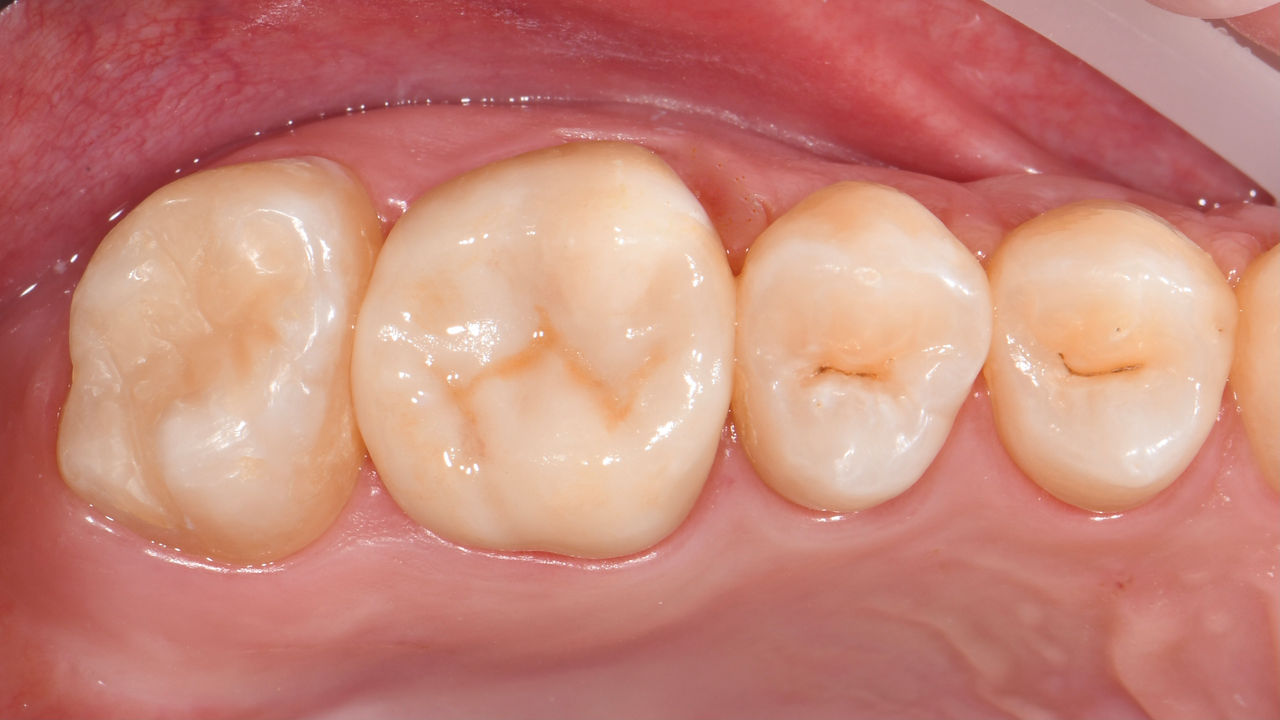

Avant : Plombages insuffisants dans le deuxième quadrant. Les restaurations avaient environ 15 ans.

Après : Couronnes fabriquées en consultation à partir du CEREC Tessera (dents 26/27). Inlays pour les dents 24 et 25 en blocs de composite.